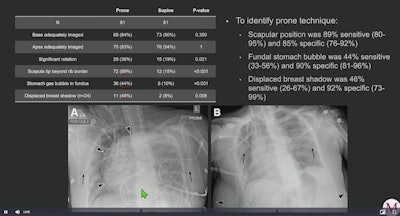

Critically ill patients underwent both supine and prone x-ray in the same day. Each set of images (81 each) was retrospectively reviewed for adequate imaging of the lungs by at least two cardiothoracic radiologists.

The reviewers found prone and supine positions were comparable for adequate imaging of the lung, with the base adequately imaged in 84% of prone images and 90% of supine images. The apex was adequately imaged in 93% of prone x-rays compared with 94% of supine x-rays, according to the findings.

However, analysis revealed the reviewers found clear position-dependent differences between prone and supine portable chest x-rays, as follows:

- Scapular tip locations beyond the rib border were greater in prone position images

- Stomach gas bubble in the fundus was greater in prone positioning images

- Displacement of one or both breast shadows in women were greater in prone position images